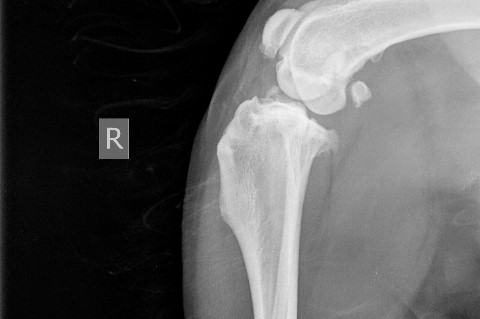

Röntgen

Ist eine bestehende Lahmheit lokalisiert, kann eine Röntgenuntersuchung sinnvoll sein, um das Ausmaß des Schadens zu ermitteln und die richtige Therapie einzuleiten. Frakturen, Luxationen und Bandabrisse sollten chirurgisch versorgt werden. Zerrungen und Prellungen benötigen meist nur Ruhe. Bei tumorverdächtigen Prozessen entscheidet das Biopsie-Ergebnis über das weitere Vorgehen.